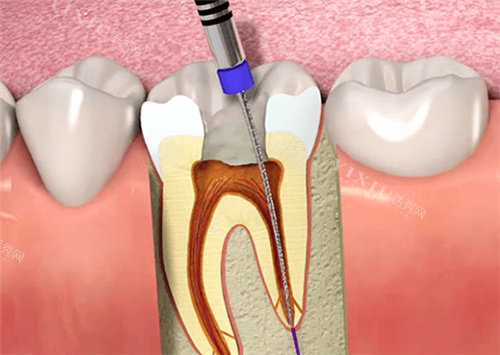

非手术再治疗:

化学辅助疏通:使用EDTA等螯合剂软化钙化组织

超声器械应用:配合特殊冲洗液震荡松解堵塞物

显微根管技术:在放大视野下精细操作

机械疏通:采用改良预备技术逐步扩通

器械使用规范:遵循小号到大型号逐步推进原则

终止标准:当达到合理疏通程度时应及时停止操作